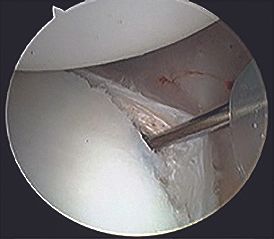

1. Arthroscopic capsulolabral repair (arthroscopic posterior Bankart)

This technique is indicated when the only damage is posterior labral detachment (Fig. 3) with no significant bone lesions. The posterior labrum can be reinserted by using anchors (Fig. 4), but posterior capsule tensioning [4] is crucial in order to recreate the glenoid concavity and restore the constraints from the capsuloligamentous structures.